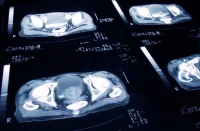

Magnetic resonance imaging (MRI) has increasingly been integrated into risk stratification protocols to improve diagnostic accuracy and guide biopsy decisions. The Prostate Imaging Reporting and Data System (PI-RADS) helps categorise lesions, but MRI findings are not always definitive, particularly in cases where background changes obscure cancerous lesions. To address these limitations, researchers have investigated additional biomarkers that may enhance MRI-based risk assessment.

A recent study explored the integration of zonal-specific PSA density (PSAD) and the Prostate Signal Intensity Homogeneity Score (PSHS) into MRI-based evaluation. These parameters could refine patient selection for biopsy by reducing false-negative MRI results and improving differentiation between benign and malignant conditions.